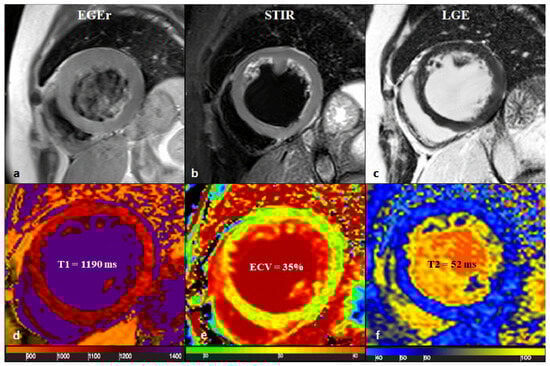

Figure 5.

A 43-year-old male patient with acute chest pain and T-Troponine release (0.05 mcg/L). The EGE ratio (a) was 5.4, with hyperemia of the anterior and infero-septal segments on the mid-ventricular plane (a, red arrows). Edema (b) with a patchy distribution on the antero-lateral and infero-septal segments (b, white arrows) was confirmed by a T2 ratio of 2.4 on the mid-ventricular plane. A non-ischemic LGE (c) was found in the inferior and infero-septal segments (c, yellow arrows) with a subepicardial distribution. Native T1 (d, mean value of 1073 ms), ECV (e, mean value of 29%), and T2 mapping (f, mean value of 51 ms) were all increased, confirming the positivity of both old and new LLC. EGE—early gadolinium enhancement, STIR—short tau inversion recovery, LGE—late gadolinium enhancement, ECV—extracellular volume fraction, and LLC—Lake Louise Criteria. Reproduced from: Cundari, G., et al. (2021). [17]. Licensed under CC BY 4.0 (https://creativecommons.org/licenses/by/4.0/ accessed on 15 December 2025).